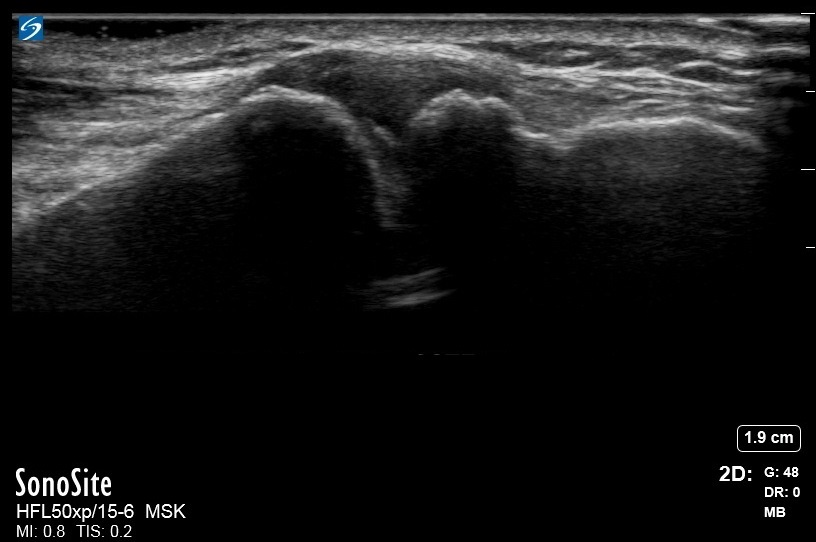

肩部患骨关节炎的肩锁 (AC) 关节图像